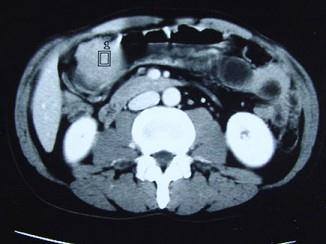

问题 女性,42岁,腹痛、黑便1周,CT扫描见胃窦部圆形块影,最佳的诊断是()

选项 A.胃窦平滑肌瘤 B.胃癌 C.胃淋巴瘤 D.胃窦神经纤维瘤 E.胃内异物

答案 D